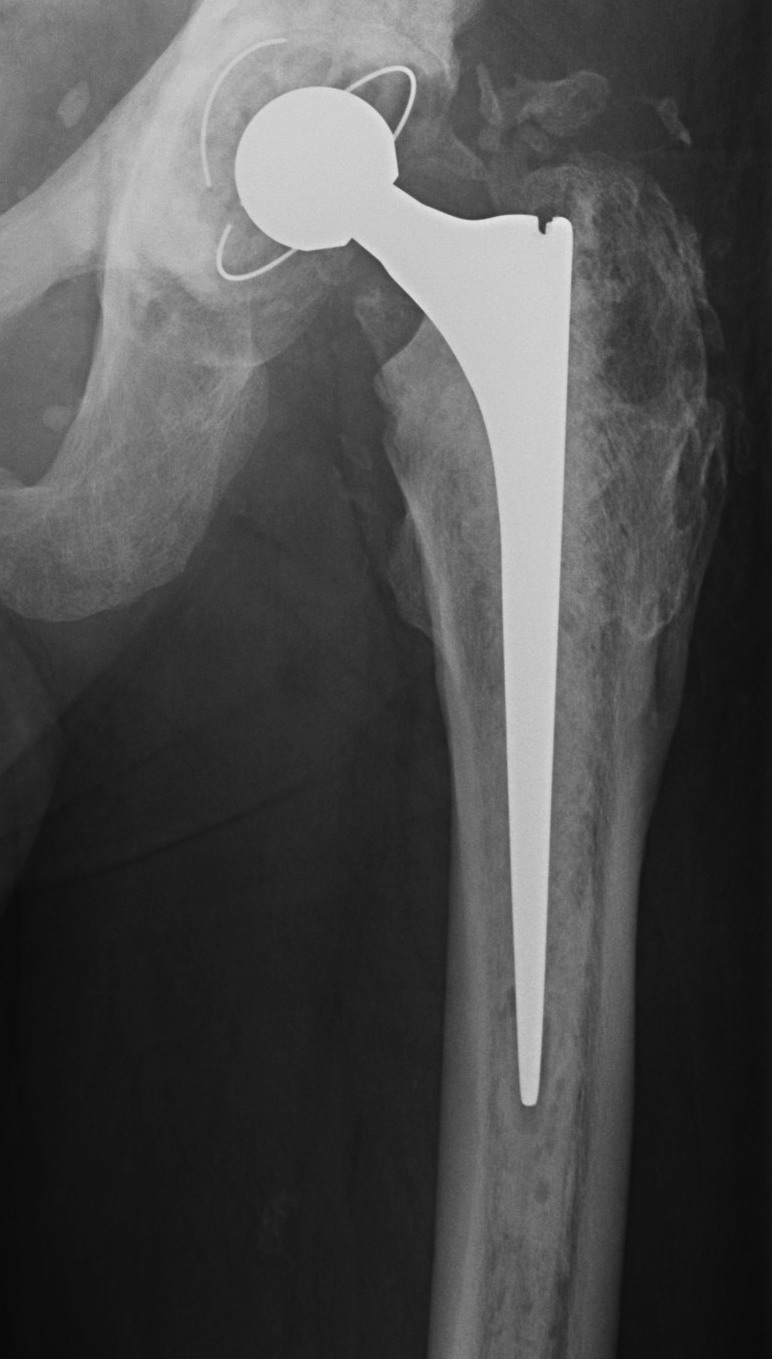

Uncemented femur

Engh classification

Types based on presence of radiolucent lines (RLL)

I.  Stable bony ingrowth

Take one year to see

A.  Spot welds at end of porous coating

B.  Absence of RLL next to porous coating

- may have RLL next to non porous coated areas

C.  Calcar atrophy secondary to stress shielding

THR Uncemented Proximal Stress ShieldingTHR Uncemented Stem Spot Weld APTHR Uncemented Stem Spot Weld Lateral

II Stable fibrous ingrowth

A.  No spot welds

B.  Parallel sclerotic lines / RLL about porous coating

C.  No migration

THR Uncemented Stem Stable sclerotic lines

III Unstable fibrous ingrowth

A.  Component migration

B.  Progressive increase RLL

- divergent RLL

C.  Pedestal formation (bony hypertrophy at tip)

THR Uncemented Subsidence